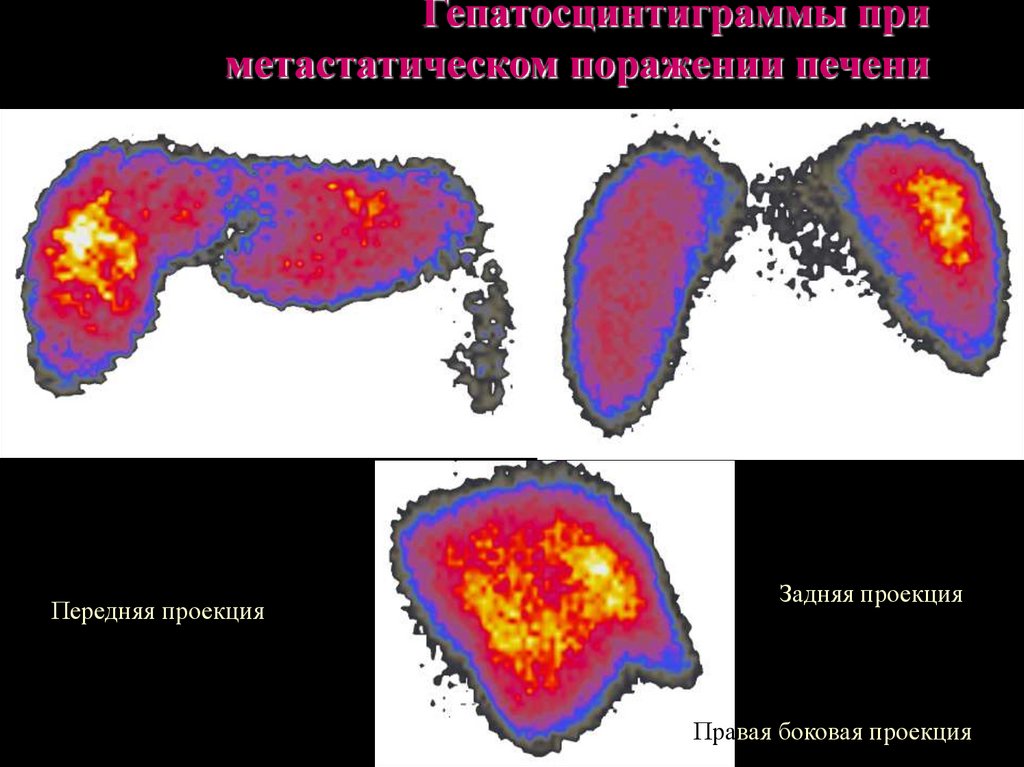

Метастатические поражения печени в ультразвуковом изображении характеризуются